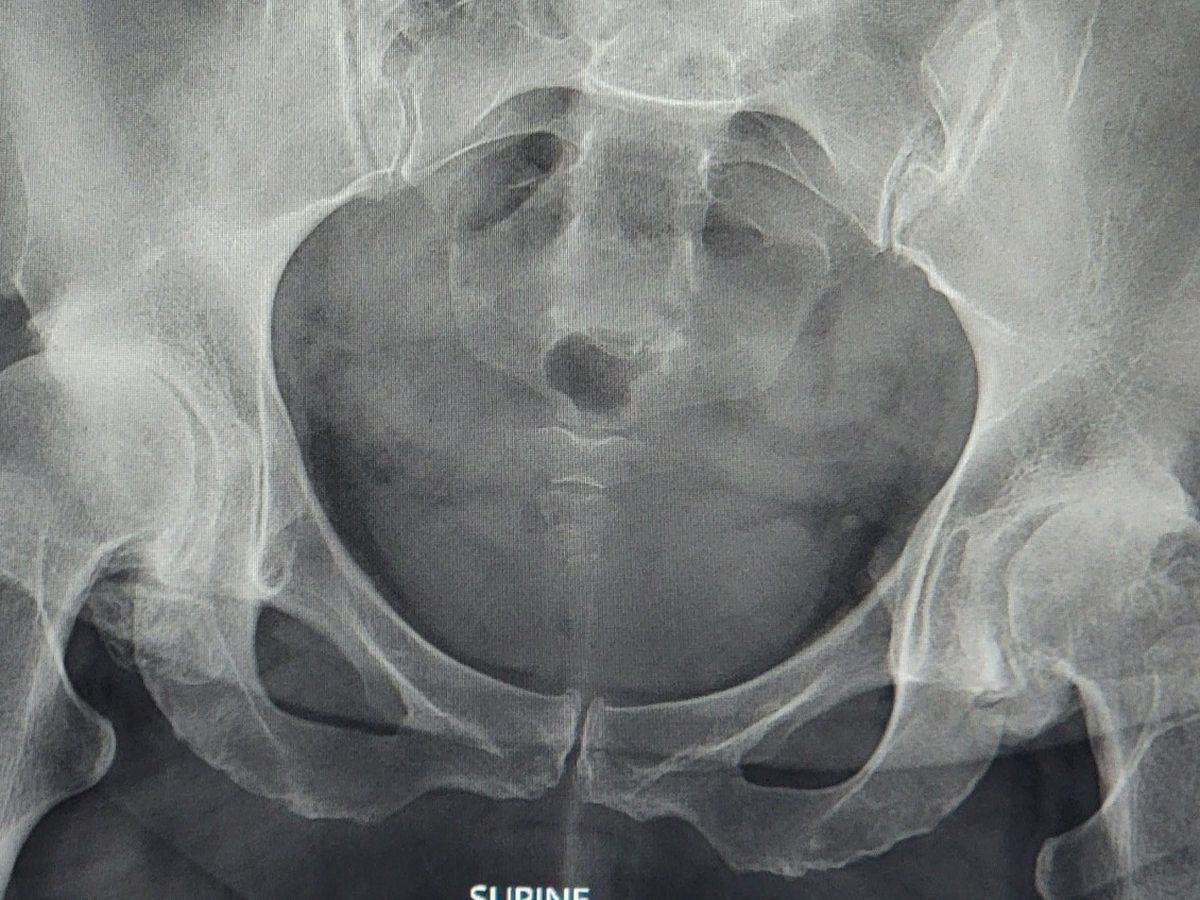

Our sassy, sweet Shalyna needs our help to get through not working, while she's waiting for her surgeries and recovery. She's been working the past couple years, past the point that she should have. Anyone who knows her knows that she is tough and almost unstopabble. Unfortunately, she is no longer physically able to work now. Fortunately, covid waits on surgery are over. The Dr's are ready to get her started on her path. Her hips don't lie, they're not even going the right direction,lol. When I saw her Xray I couldn't believe she was working like that! But, providing for her family was so important to her that she set all that pain aside. And even made jokes and laughed her way through it. She's a huge inspiration to me and probably the person reading this too. She's been so generous; it's time for us to give back to her for once. Thoughts and prayers are great, but I'm asking for cash money, lol. But seriously, let's all help out our girl! Much love Shalyna!